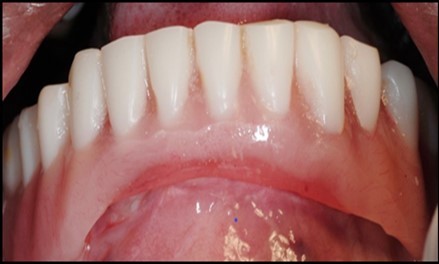

A transferable mark with an indelible pencil is placed on top of each ball abutment and old denture is seated to ideally determine the location for attachment housings. It is followed by preparation of recesses in the intaglio surface of the denture to accommodate the housings (Figure 7B). Lingual vent holes are made for escape of excess acrylic. Placement of nylon processing insert into each of the housings is done with insert seating tool. Figure 8 Seating of the attachment housing onto each ball type abutment is done (Figure 9). Undercuts are blocked out under the housing and soft tissue to prevent acrylic resin from locking the denture onto the abutment. Application of self curing acrylic is done into recessed area and around titanium housings for bonding of the housings to denture. Insertion of denture was done and guiding the patient into proper occlusion with the opposing arch. After the curing of acrylic, denture is removed. Excess acrylic is removed around the housings and lingual vent hole later it is polished (Figure 10). Replace nylon retention insert instead of processing insert into the housings. The insert must seat securely in place and be in level with the housings rim. Overdenture is seated over the ball abutments (Figure 11). Proper instructions have been given to the patient on insertion and removal of prosthesis (Figure 12). The patient was recalled at 1 week, 3 weeks, 3 months, 6 months follow up appointments.

Figure 11.View of denture after being cleaned and polished